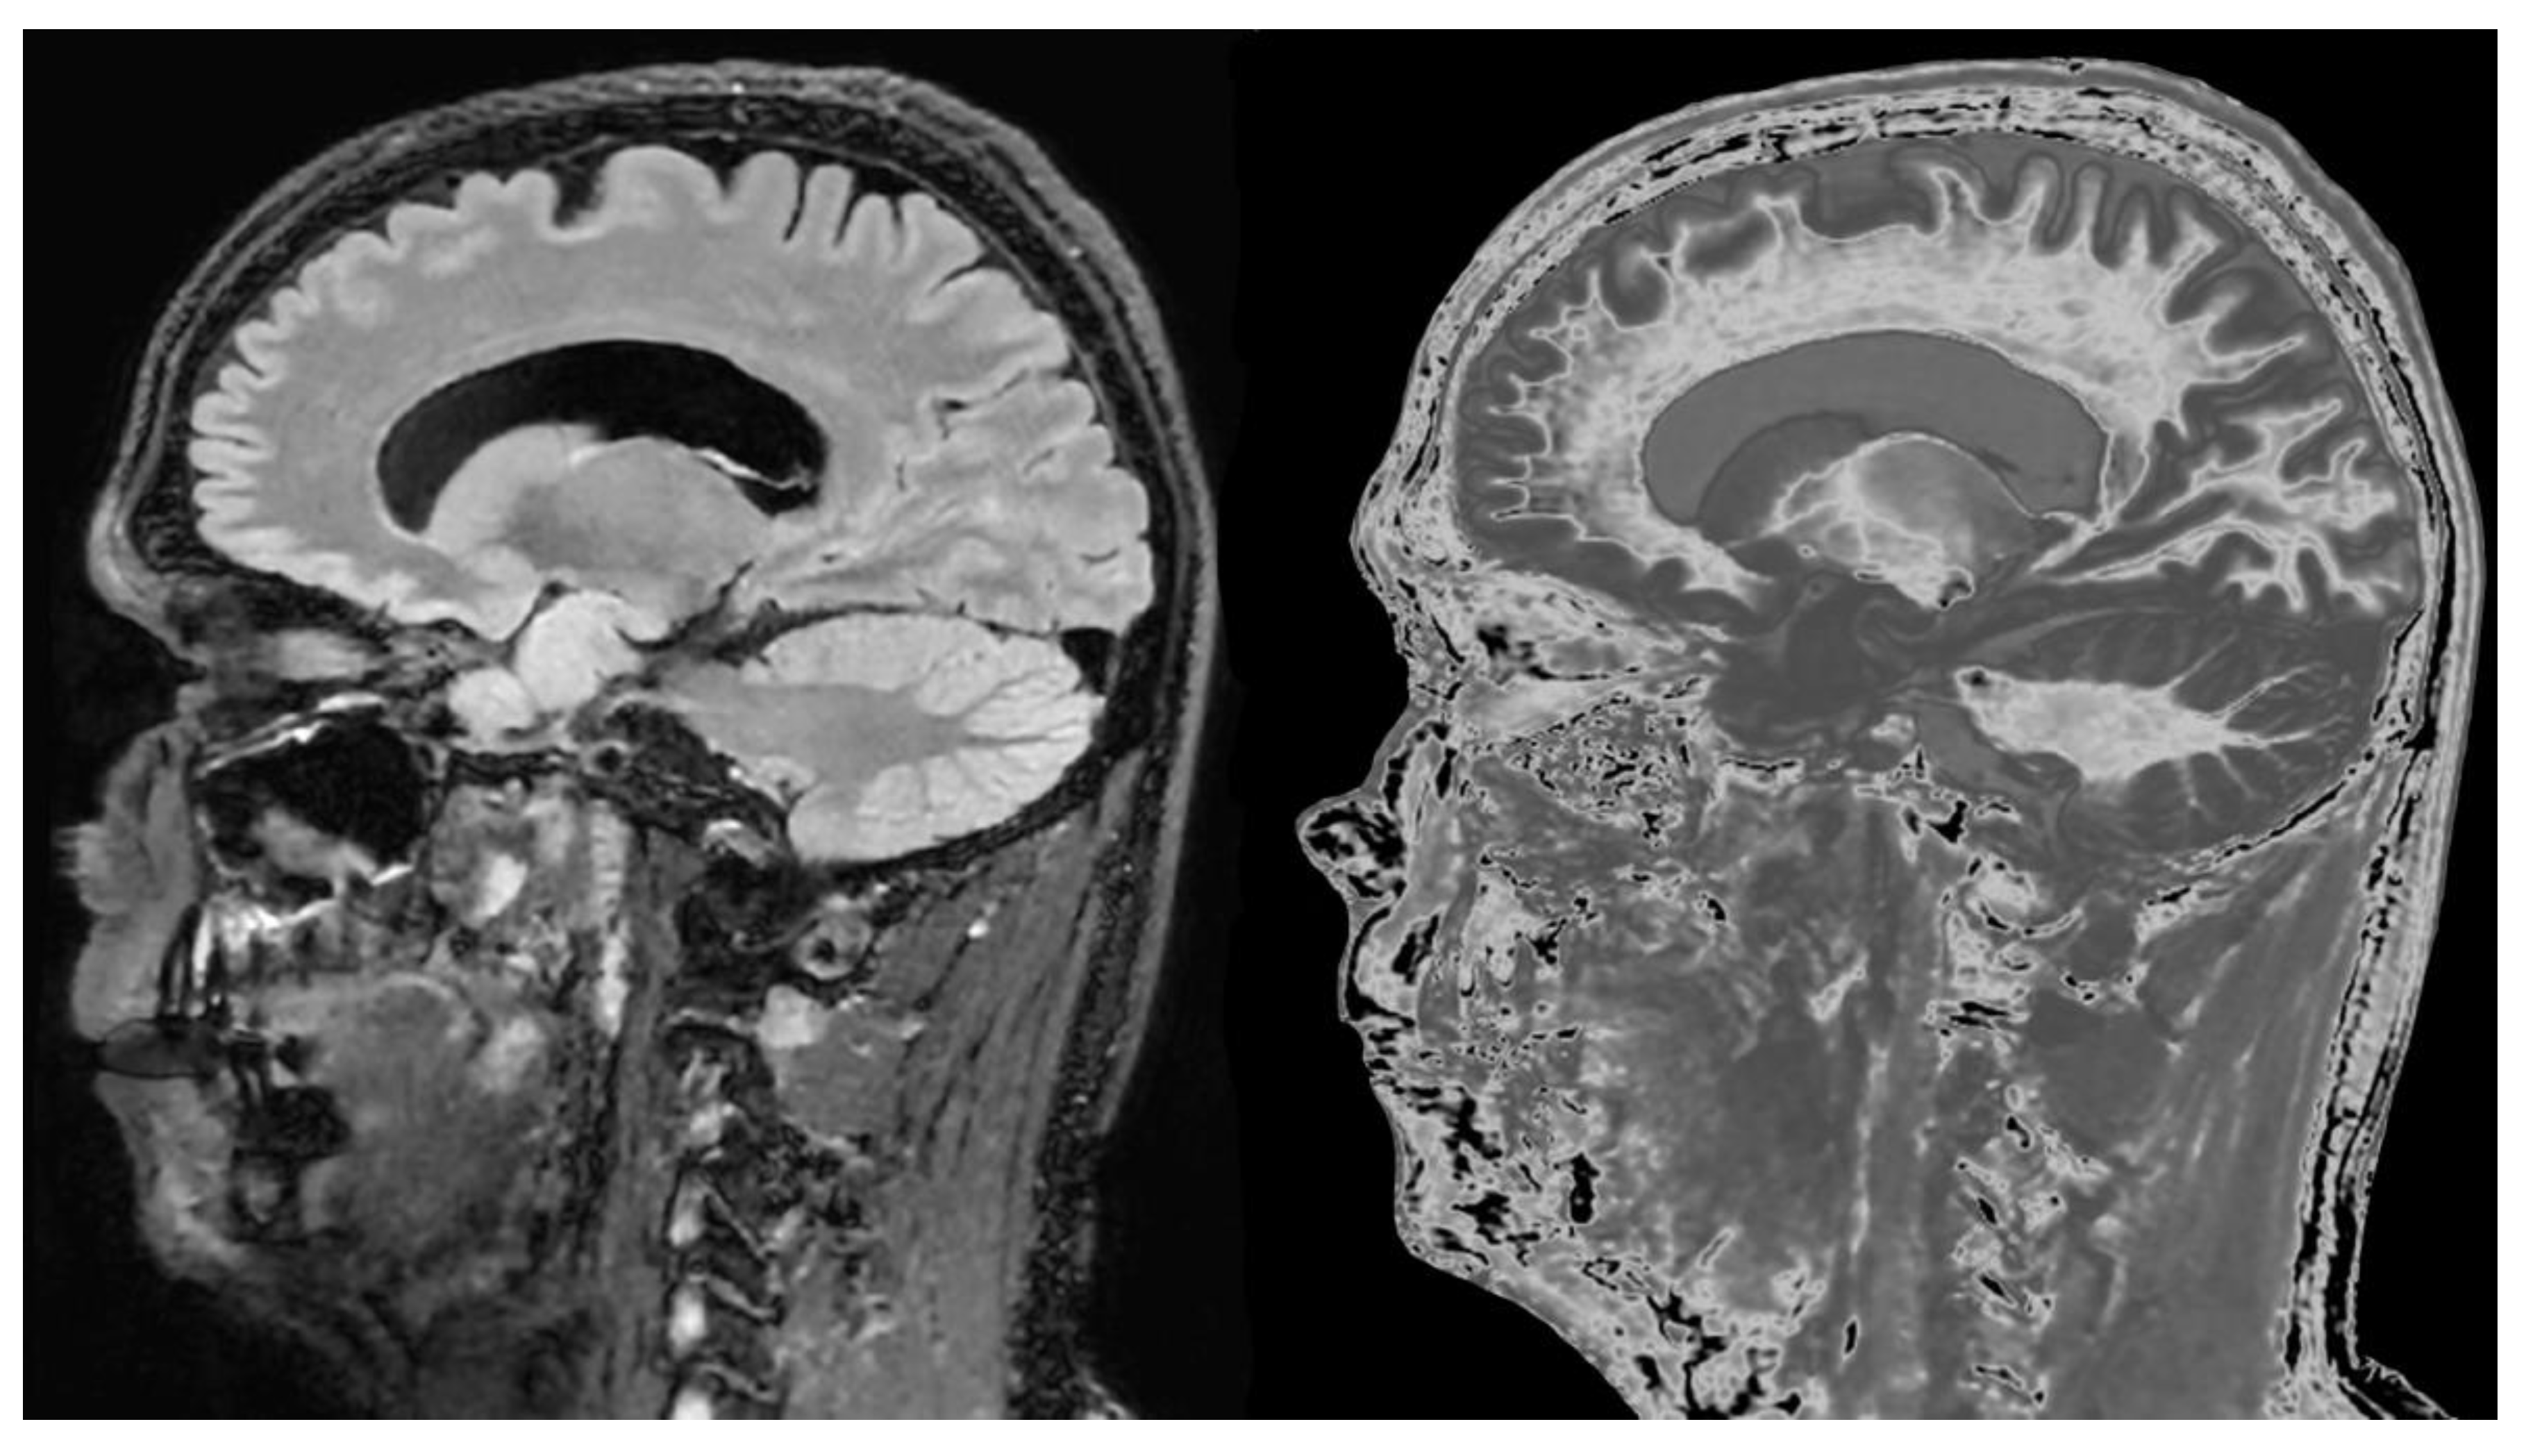

- Ultra-high contrast MRI using bipolar filters (BLAIRs) can show abnormalities with very high contrast where little or no change from normal is seen with common conventional state-of-the-art sequences.

- The abnormalities shown with ultra-high contrast are due to small changes in tissue properties such as T1 and T2 in disease. This is complementary to existing sequences which show abnormalities due to larger changes in T1 and T2 in disease.

- At boundaries between tissues and fluids on ultra-high contrast images there is frequently an increase in contrast and an increase in the spatial resolution of that contrast.

- Extensive abnormalities were seen in mild traumatic brain injury, multiple sclerosis and white matter associated with cerebral tumours in the absence of changes in T2-weighted spin echo or T2-FLAIR images.